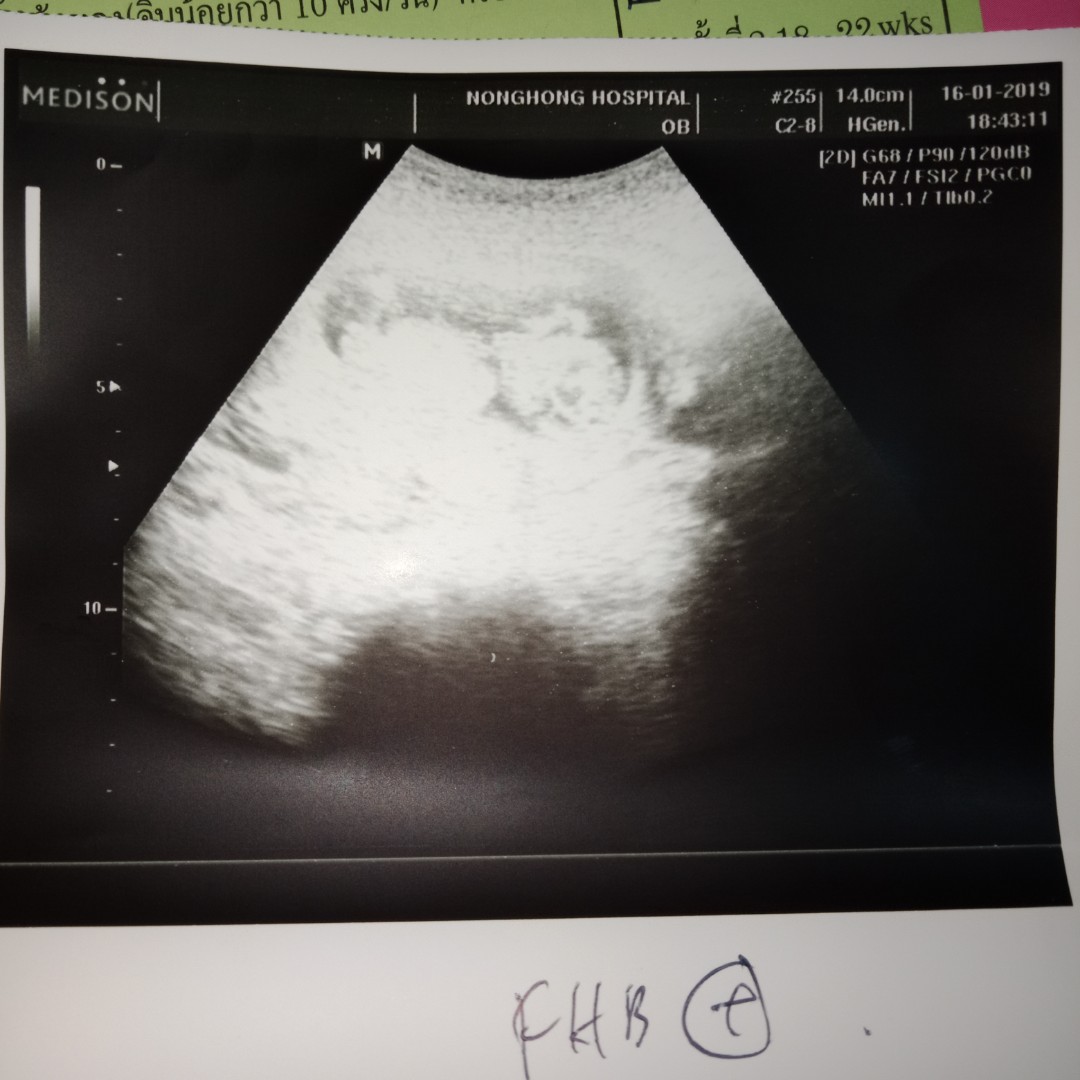

บ้านนี้ตอน 10w ค่ะ